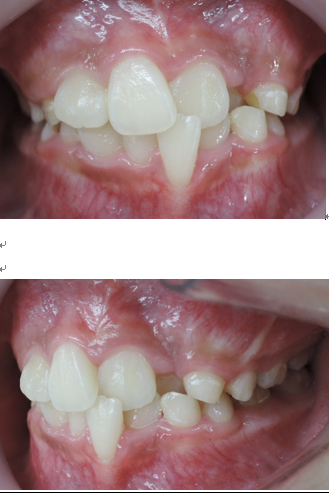

今回の症例は、悪い歯並びの代表例である八重歯です。

歯並びが悪いだけでなく、困ったことに犬歯から奥歯にかけて歯が嚙み合っていない開咬の状態です。

当院ではマルチループ(MEAW法)という上の写真で装着しているようなクネクネ曲がったワイヤーを使用して、上下の隙間を埋めていくことで歯並びを整えます。